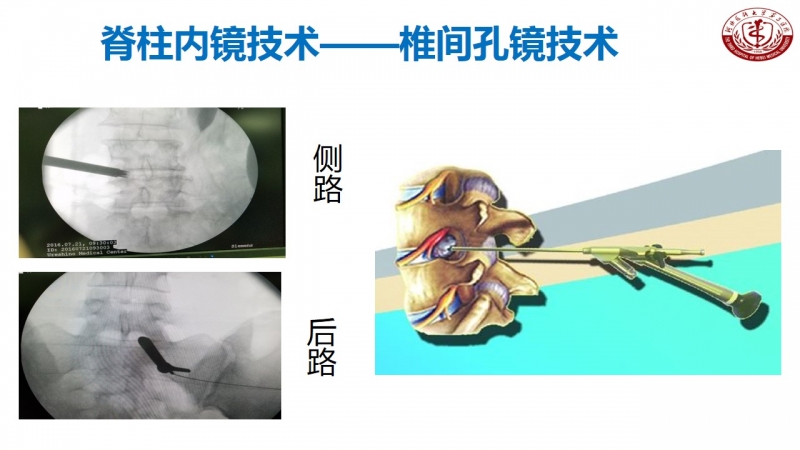

其实,在河北医科大学第三医院脊柱外科不乏这样的新技术创新。丁文元教授从医33年来,在脊柱疾病相关基础临床研究和治疗中做了大量的工作。

核心技术展示

科室发展,未来可期

脊柱外科目前所开展的诊疗技术(滑动查看)

相信河北医科大学第三医院脊柱外科在新的学科带头人的领导下,不忘初心,砥砺前行,做好脊柱基础及临床研究,逐步提高学术影响力,攻克临床上各个难关,提升临床诊疗水平,使脊柱外科朝着精准化、微创化、显微化、智能化发展,造福更多患者。